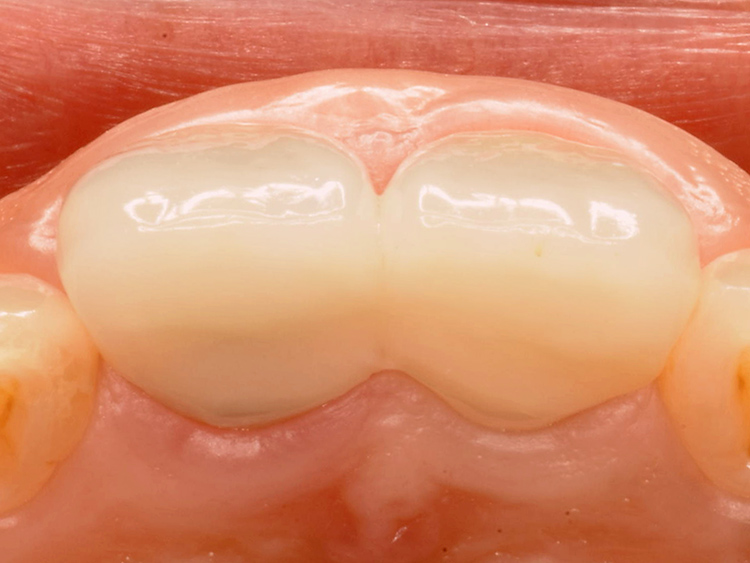

仮歯を調整しながら厚みのある歯周組織を誘導します

歯根破折部に隣接する歯肉は、赤く炎症を起こし損傷していました。

歯肉の健全な厚みや歯根への付着が失われ、細菌感染に対するバリア機能も低下していました。せっかく歯を保存し修復できたとしても、その後に虫歯や歯周病を再発させては意味がありません。

最終的なセラミックス冠を装着する前に、仮歯の形態を調整しながら、健全な歯周組織の回復を誘導します。

炎症を起こし赤みを帯びていた歯肉は、徐々にピンク色に引き締まり、厚みが回復してきました。健全に回復した歯肉からは、細菌侵入に抵抗する白血球を豊富に含む滲出液が分泌され、これにより治療後の虫歯や歯周病の予防効果が高まります。